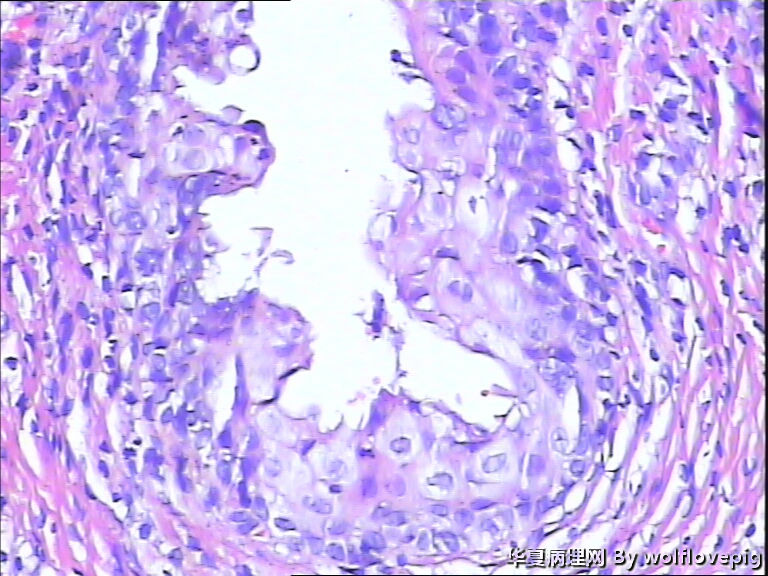

31y,阴蒂附近囊肿2.0*1.5cm

外阴最常见的囊肿是前庭大腺囊肿,囊肿一般衬以移行上皮,常伴有非角化性鳞状化生,也有的呈扁平或立方状,囊肿周边附近可以见到黏液腺体。

此例有点特殊,看到一些纤毛柱状上皮被覆,称为纤毛囊肿,属于前庭大腺囊肿的特殊改变。

前庭大腺囊肿位于外阴后半部,而此例位于阴蒂附近。

泌尿生殖窦起源的外阴囊肿(粘液性和纤毛囊肿)

1,多见于21-30及31-40的多产妇女,病变多位于外阴前庭。

2,组织学上,粘液性囊肿含有与宫颈内膜或阴道腺病一样的粘液性上皮内衬,少数情况下可出现鳞状上皮化生。也有报道有些病例出现纤毛细胞,可以与粘液上皮混合存在。